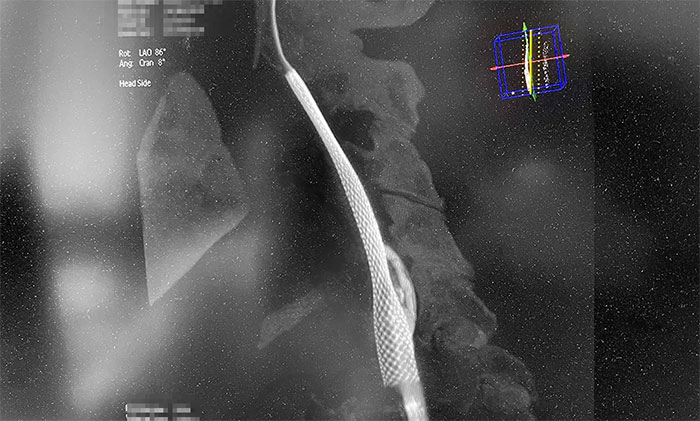

術(shù)中,超滑導(dǎo)絲、多功能導(dǎo)管經(jīng)過反復(fù)嘗試順利通過左頸內(nèi)動(dòng)脈起始段,到達(dá)左頸內(nèi)動(dòng)脈遠(yuǎn)端顯影段,路圖見遠(yuǎn)端血管通暢,左大腦中動(dòng)脈顯影;隨后,微導(dǎo)絲經(jīng)多功能導(dǎo)管置于左頸內(nèi)動(dòng)脈海綿竇段,經(jīng)微導(dǎo)絲送入保護(hù)傘至左頸內(nèi)動(dòng)脈巖骨垂直段并釋放,再沿保護(hù)傘微導(dǎo)絲送入4x30mm球囊于左頸內(nèi)動(dòng)脈起始段,給予球囊擴(kuò)張,撤除球囊后造影見左頸內(nèi)動(dòng)脈起始段再通,左頸內(nèi)動(dòng)脈、左大腦中動(dòng)脈顯影;最后,送入9x50mm支架,釋放于左頸內(nèi)動(dòng)脈頸段至左頸總動(dòng)脈末段,造影見左頸內(nèi)動(dòng)脈起始段顯影明顯改善,左頸內(nèi)動(dòng)脈、左大腦中動(dòng)脈、左大腦前動(dòng)脈顯影可,行3D造影見左頸內(nèi)動(dòng)脈頸段顯影改善。行支架CT見支架成形可,行XperCT未見顱內(nèi)出血。

▲ 左側(cè)頸內(nèi)動(dòng)脈閉塞順利開通

手術(shù)圓滿完成,席剛明教授團(tuán)隊(duì)、麻醉科團(tuán)隊(duì)及導(dǎo)管室團(tuán)隊(duì)通力合作,耐心、仔細(xì)地克服了手術(shù)的所有難點(diǎn)。左頸內(nèi)動(dòng)脈從“無”到“有”,正所謂“精誠(chéng)所至,金石為開”,順利為患者解除危機(jī)。